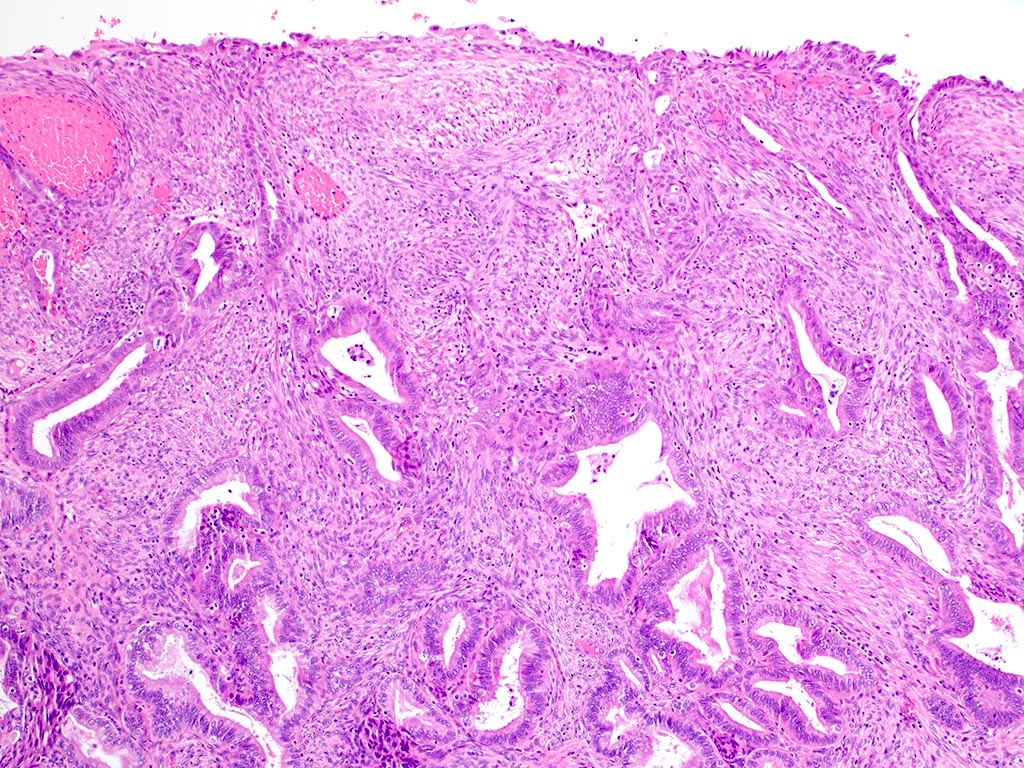

Microscopic (histologic) description

- Biphasic tumor:

- Endometrioid glands, usually with complex architecture and sometimes with cytologic atypia

- Glandular component often shows lobulated architecture

- Benign fibromyomatous stroma, rarely with myxoid change

- Squamous morular metaplasia is frequently seen and may show central necrosis

- Well circumscribed or slightly irregular margin

- Reference: Am J Surg Pathol 2015;39:1148

Microscopic (histologic) images